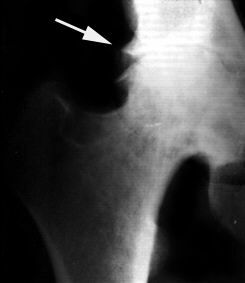

Рентгенодиагностика остеоартроза

Костные суставные поверхности, лишенные амортизации из-за деструкции хрящевой ткани, испытывают повышенную и неравномерную механическую нагрузку. В субхондральной кости появляются зоны динамической перегрузки, которые вызывают перераспределительные нарушения микроциркуляции. Это способствует возникновению субхондрального остеосклероза, кистовидной перестройки, изменению кривизны суставных поверхностей и образованию краевых костно-хрящевых разрастаний — остеофитов.